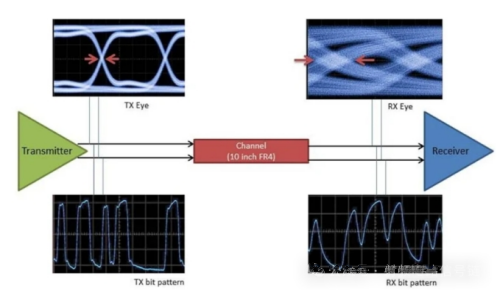

fMRI的工作原理是通过产生底层磁场来影响大脑中分子的方向。如果一个磁场被设置为可预测的模式,就可施加第二磁场,快速振荡磁场方向,区分人脑组织的密度或类型。人们开发了各种技术,可使用血流或血氧水平作为大脑活动的指标。

法因贝格说,NexGen 7T包括一个新的梯度线圈,它设置了底层磁场的模式。研究合作者、加州大学旧金山分校的放射学家安•T. 乌(An T. Vu)表示,该线圈可能是新元件中最新颖的设计,其中增加了第三层绕组和重新设计的冷却系统。控制第二磁场的发射系统和射频接收阵列都进行了扩展,分别达到16至128通道,这至少是普通研究型MRI扫描仪的2倍。不过,这些改变带来了与数据采集、传输和编码有关的新挑战。

“当有128个接收器时,数据量会呈指数级增长。”乌说,“实际上,数据存储和计算资源也需要跟上。”